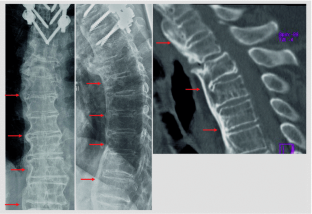

Abb. 1